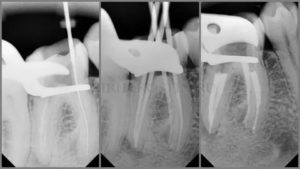

РИС.5 После удаления старой гуттаперчи инструмент был найден при помощи Gates Glidden.3 и стал визуализироваться под микроскопом (второе изображение).

Ультразвуковое препарирование для создания промежутка и освобождения инструмента от стенок дентина (третье изображение).

ПРИМЕЧАНИЕ: ультразвуковую обработку проводили только по внутренней стенке без движений против часовой стрелки для большего сохранения дентина (проследите на рентгеновском снимке после операции на предыдущем изображении).

РИС.6 – Верхний 7ой зуб с 2 сломанными инструментами в средней трети дистального канала. 2 фрагмента были успешно удалены с помощью увеличения и ультразвука. После подготовки крошечного пространства на внутренней стенке раствор ЭДТА был использован с ультразвуковой активацией для легкого продвижения инструмента в сторону пульповой камеры.

РИС.7 – ПРИМЕЧАНИЕ: ультразвуковая подготовка пространства на внутренней стенке (второе изображение, желтая стрелочка).